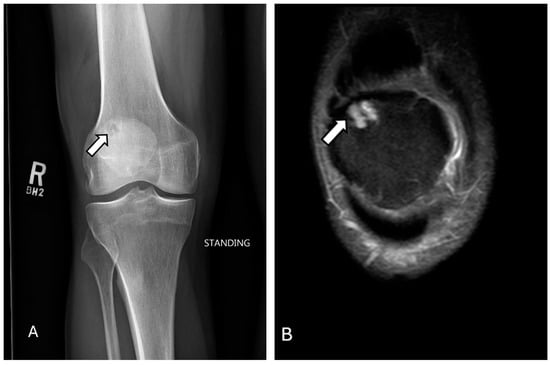

3.4. Osteochondral Injury